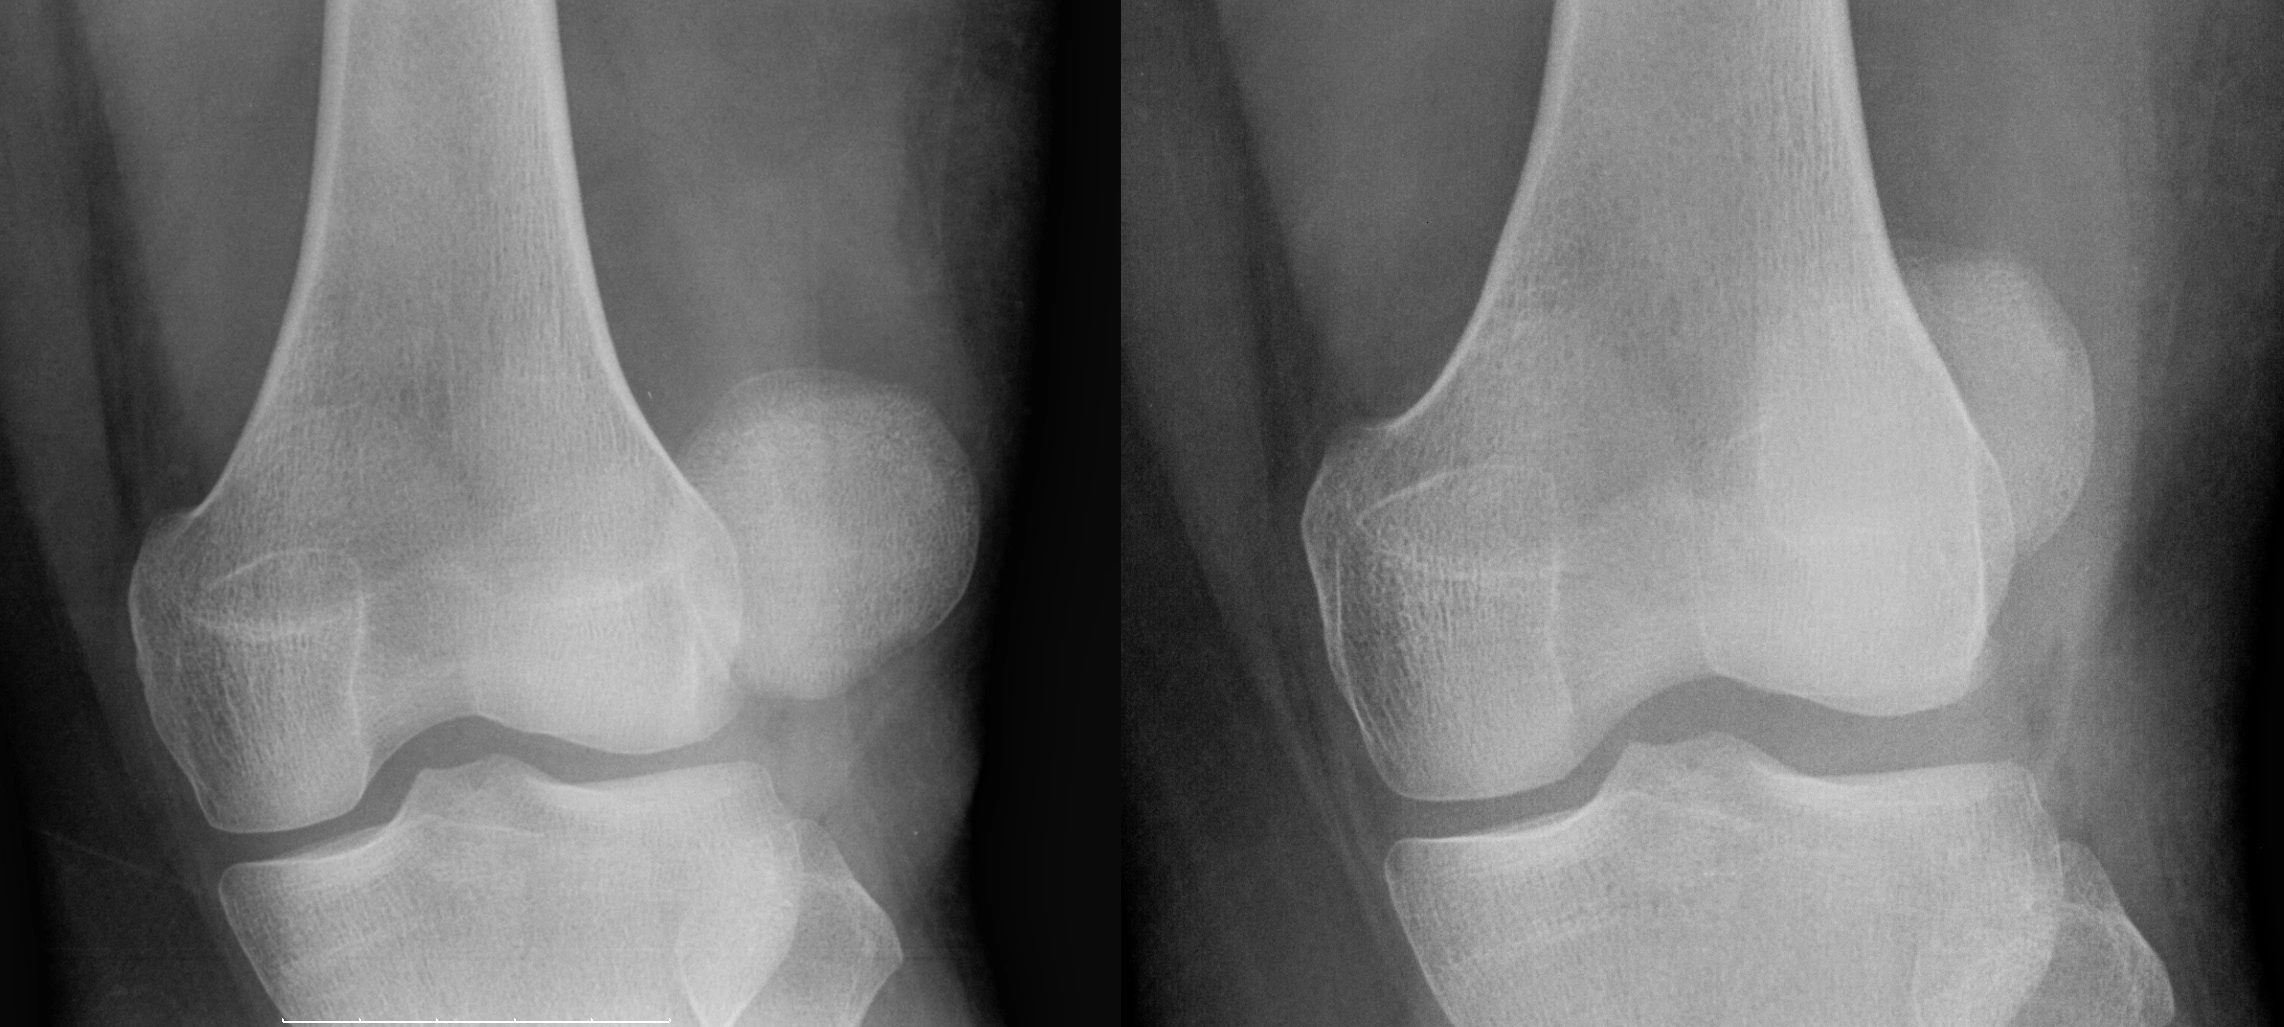

در حالت طبیعی، کشکک با هدایت رباطها و عضلات اطراف آن، در مسیر مشخصی حرکت میکند اما اگر در اثر ضربه مستقیم، پیچش ناگهانی زانو یا ضعف ساختاری، از شیار اصلی خود خارج شود، به آن دررفتگی کشکک زانو (Patellar Dislocation) گفته میشود. همانطور که در عکس دررفتگی کشکک زانو مشخص است، کشکک زانو جا به جا شده است و برای درمان، پزشک باید آن را جا بیندازد و به جای اصلی برگرداند.